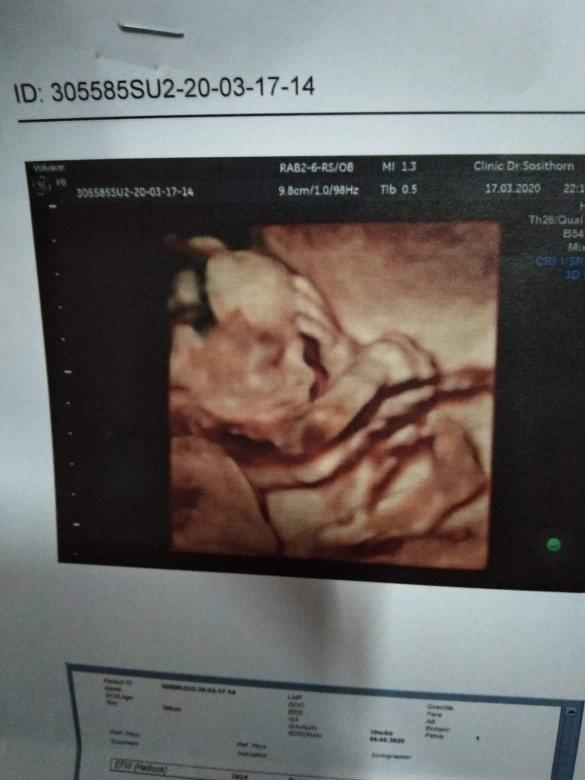

20+6.เพศชายจ้ะ